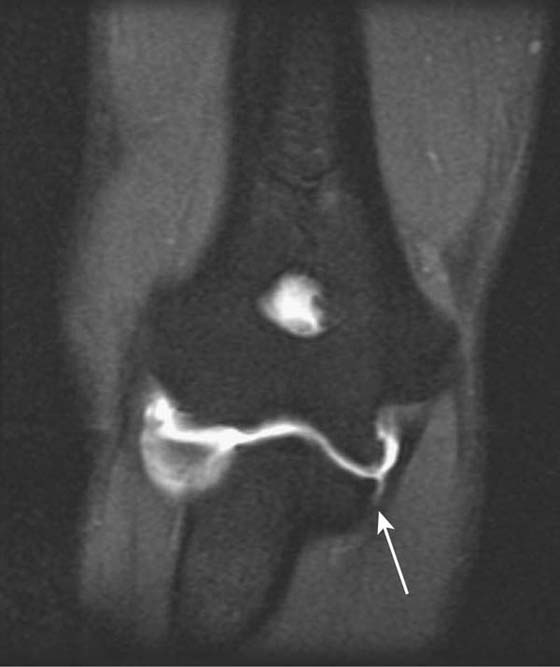

Injury to Medial and Lateral Stabilizing Ligaments

Direct MR arthrography is most useful in detecting suggested injury to the medial and lateral stabilizing ligaments. The medial (ulnar) collateral ligament, for example, is frequently injured in baseball pitchers and can be assessed accurately with MR arthrography34-36 (Fig. 14-13). US is also useful in assessing the elbow ligaments but has an advantage over MRI with its ability to assess ligamentous laxity in real time with dynamic imaging37,38 (Fig. 14-14). For example, during valgus stress for assessment of the medial collateral ligament, a difference in 2 mm between sides is diagnostic of abnormal ligamentous laxity.

images

Figure 14-13 Ulnar collateral ligament tear. Coronal fat-suppressed T1-weighted image of the elbow after intra-articular gadolinium injection (direct MR arthrogram) demonstrates abnormal tracking of contrast (arrow) between the anterior bundle of the ulnar collateral ligament and the coronoid process of ulna at the sublime tubercle, indicating a distal partial thickness undersurface tear.